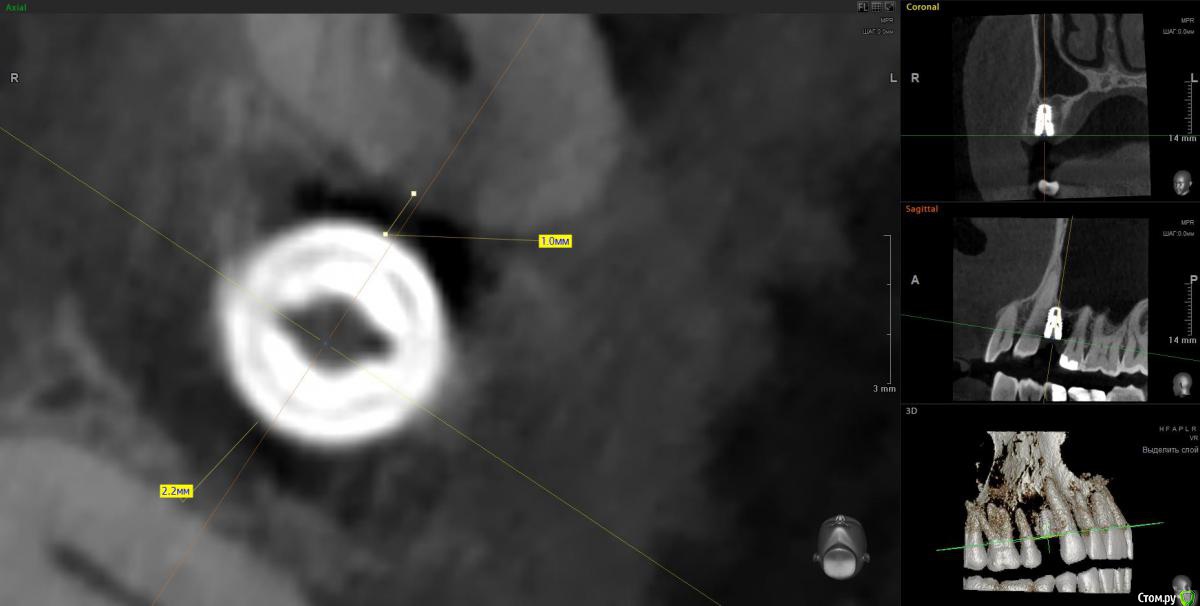

It'sGeorgy Опубликовано 14 апреля, 2020 Поделиться Опубликовано 14 апреля, 2020 Вчера одномоментно. кт только сегодня. Жалоб нет. Хотя там и сст с неба. конечно клык не сверленый, но близость напрягает. Съехал он при установке. Поленился снимок делать после установки, ушил лунку с трансплантатом, во рту норм выглядел. А потом на рг не очень) контроль кт Оставить? убрать недели через 3?Если есть уверенность, что в следующий раз получится поставить лучше и успешно провести ЗСЛ - я бы убрал. Какие показания к удалению? Я бы оставил, не вижу проблемы 0.7 мм рисково между зубов и винтом, на мой взгляд оставлять. Ну и по глубине тоже, ябдокрутил. Ссылка на комментарий

Doctor Vlad Опубликовано 14 апреля, 2020 Поделиться Опубликовано 14 апреля, 2020 Если есть уверенность, что в следующий раз получится поставить лучше и успешно провести ЗСЛ - я бы убрал. 0.7 мм рисково между зубов и винтом, на мой взгляд оставлять. Ну и по глубине тоже, ябдокрутил. было такое в практике, чем опасно? Ссылка на комментарий

Irouil Опубликовано 14 апреля, 2020 Поделиться Опубликовано 14 апреля, 2020 глубины мало?Платформа впритык к зубу, риск формирования кармана очень велик 1 Ссылка на комментарий

Irouil Опубликовано 15 апреля, 2020 Поделиться Опубликовано 15 апреля, 2020 Объясните-в чем опасность? Не понимаю...На уровне шейки, на мой взгляд, будет карман. По вертикали не хватит тканей чтобы обеспечить биологическую ширину Ссылка на комментарий

Doctor Vlad Опубликовано 16 апреля, 2020 Поделиться Опубликовано 16 апреля, 2020 Объясните-в чем опасность? Не понимаю...С зубом проблем не будет, имплант без компрессии там лежит и не травмирует. Но в плане протезирования и долгосрочной перспективы хочется видеть его ровней и на равном удалении от зубов. следующий имплант будет уже. ось его на центр выходит между 13 и 15 но 1 мм от платформы до 13 зуба маловато. Опыта в таких случаях нет. В нижних резцах тоже бывает меньше мм 1 остается и все норм. Хотелось бы поглубже. Сейчас он на мм 2 заглублен от кортикалки и мм 3.5 по десне. но пройдет ремоделировка и будет меньше, а может и нет. Если бы я его протезировал может быть оставил бы посмотреть. Ссылка на комментарий